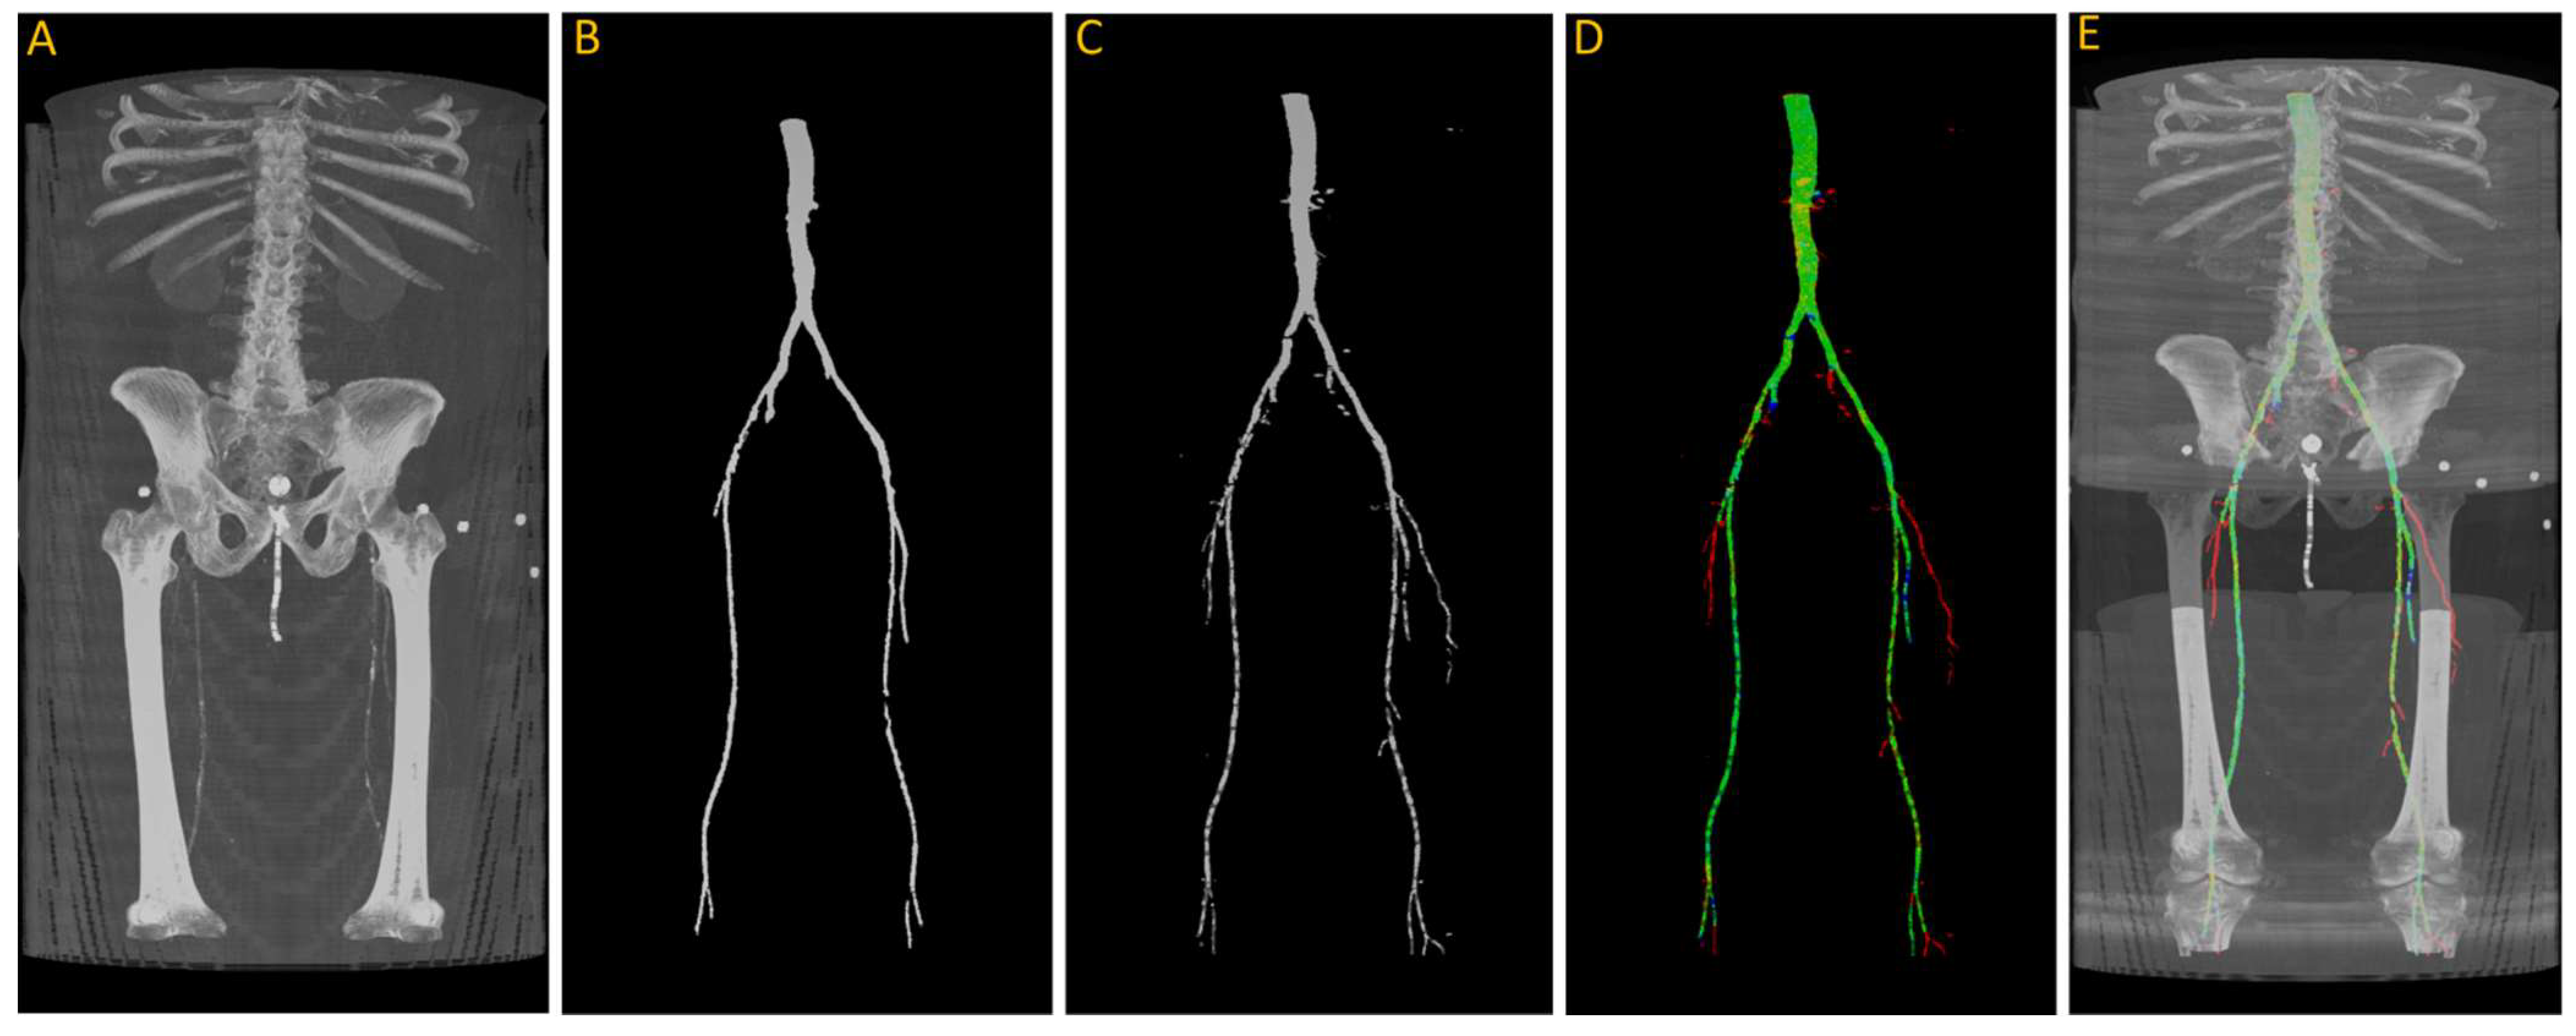

In this paper, we train a deep learning model to automatically extract the vascular system from CT images. Subsequently, we employ thresholding techniques to identify vascular calcifications and provide an automated lower extremity calcification score, as illustrated in Figure 1. We also analyze the performance of deep learning models and evaluate their accuracy and reliability through performance analysis. This fully automated process enables the accurate calculation of lower extremity calcium scores within a matter of seconds. The developed DNN model and related documentation in this project are available at https://github.com/pip-alireza/DeepCalcScoring. In summary, our contributions are as follows:

Figure 1.

Workflow of the proposed model for quantifying lower extremity calcification. (A) Input image is processed by the deep learning model (B) to automatically segment the vascular system, which is overlaid on the input image to extract the vascular system (C). Subsequent intensity thresholding (D) with a threshold value of 145 is applied to extract calcifications within the extracted vascular system (E). Finally, the cumulative calcification score is obtained by aggregating individual calcifications (F), and a conversion factor is applied to measure calcium volume (G).